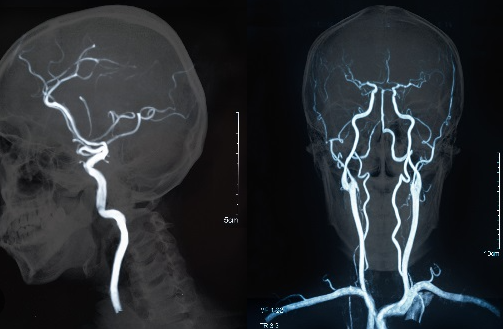

허혈성 뇌졸중은 뇌혈관이 막히는 경우 발생합니다. 뇌혈관 내부에 혈전이 생기면 혈액이 뇌로 흐르지 못하게 막을 수 있습니다.

출혈성 뇌졸중은 뇌혈관이나 혈관 주변 조직이 파열되는 경우 발생합니다. 파열된 혈관에서 피가 새어 나와 뇌를 손상시키는 것입니다.

- 혈액 검사와 뇌 전산화 단층촬영(CT)을 시행합니다.

3. 혈관 내시경 검사 및 혈관 스텐트 삽입

- 혈전용해제제로 효과가 없는 경우, 혈관 내시경 검사와 혈관 스텐트 삽입 등의 치료가 필요합니다.

- 혈관 내시경 검사를 통해 혈관의 혈액 흐름을 확인하고, 혈관 스텐트를 삽입해 혈액 흐름을 개선합니다.